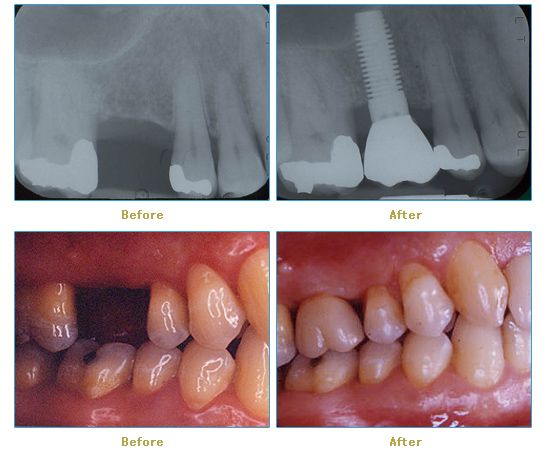

Dr. Cabianca has restored hundreds of smiles through the latest techniques in restorative and cosmetic dentistry. The following before and after photos document a few such cases in which Dr. Cabianca has replaced and reshaped teeth to produce wonderful smiles. Click on any of the images below to view larger versions of the photos.